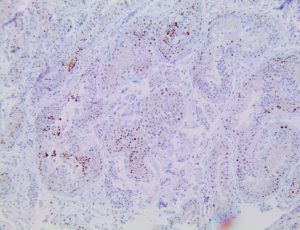

The first cytokines released are interleukin 1β (IL-1β) and tumor necrosis factor-α (TNF-α), which attract a variety of circulating white blood cells (WBCs) to the infection site, including neutrophils, monocytes, macrophages, and natural killer (NK) cells. This response, along with the antipathogenic chemicals released by these cells (i.e., complement), comprise the innate immune response. These cells directly attack the invading pathogen and also release additional cytokines, chief among them interleukin-1 and 6 (IL-6). IL-6 is essential for invoking the adaptive immune response, which calls T-cells, B-cells, and T helper (Th) cells to the infection site. IL-6 also stimulates further recruitment, proliferation and activation of macrophages.

It is the ICU physician who is most likely to witness one of the deadliest manifestations of the abnormal immunological response, the cytokine storm syndrome (CSS). This response is also referred to by some as the cytokine release syndrome (CRS). CSS is characterized by continuous activation and expansion of macrophage and lymphocyte populations, which secrete large amounts of cytokines, causing the cytokine storm. This massive cytokine release is akin to hemophagocytic lymphohistiocytosis (HLH) disease, a syndrome characterized by initial unchecked and persistent activation of cytotoxic T lymphocytes and NK cells.